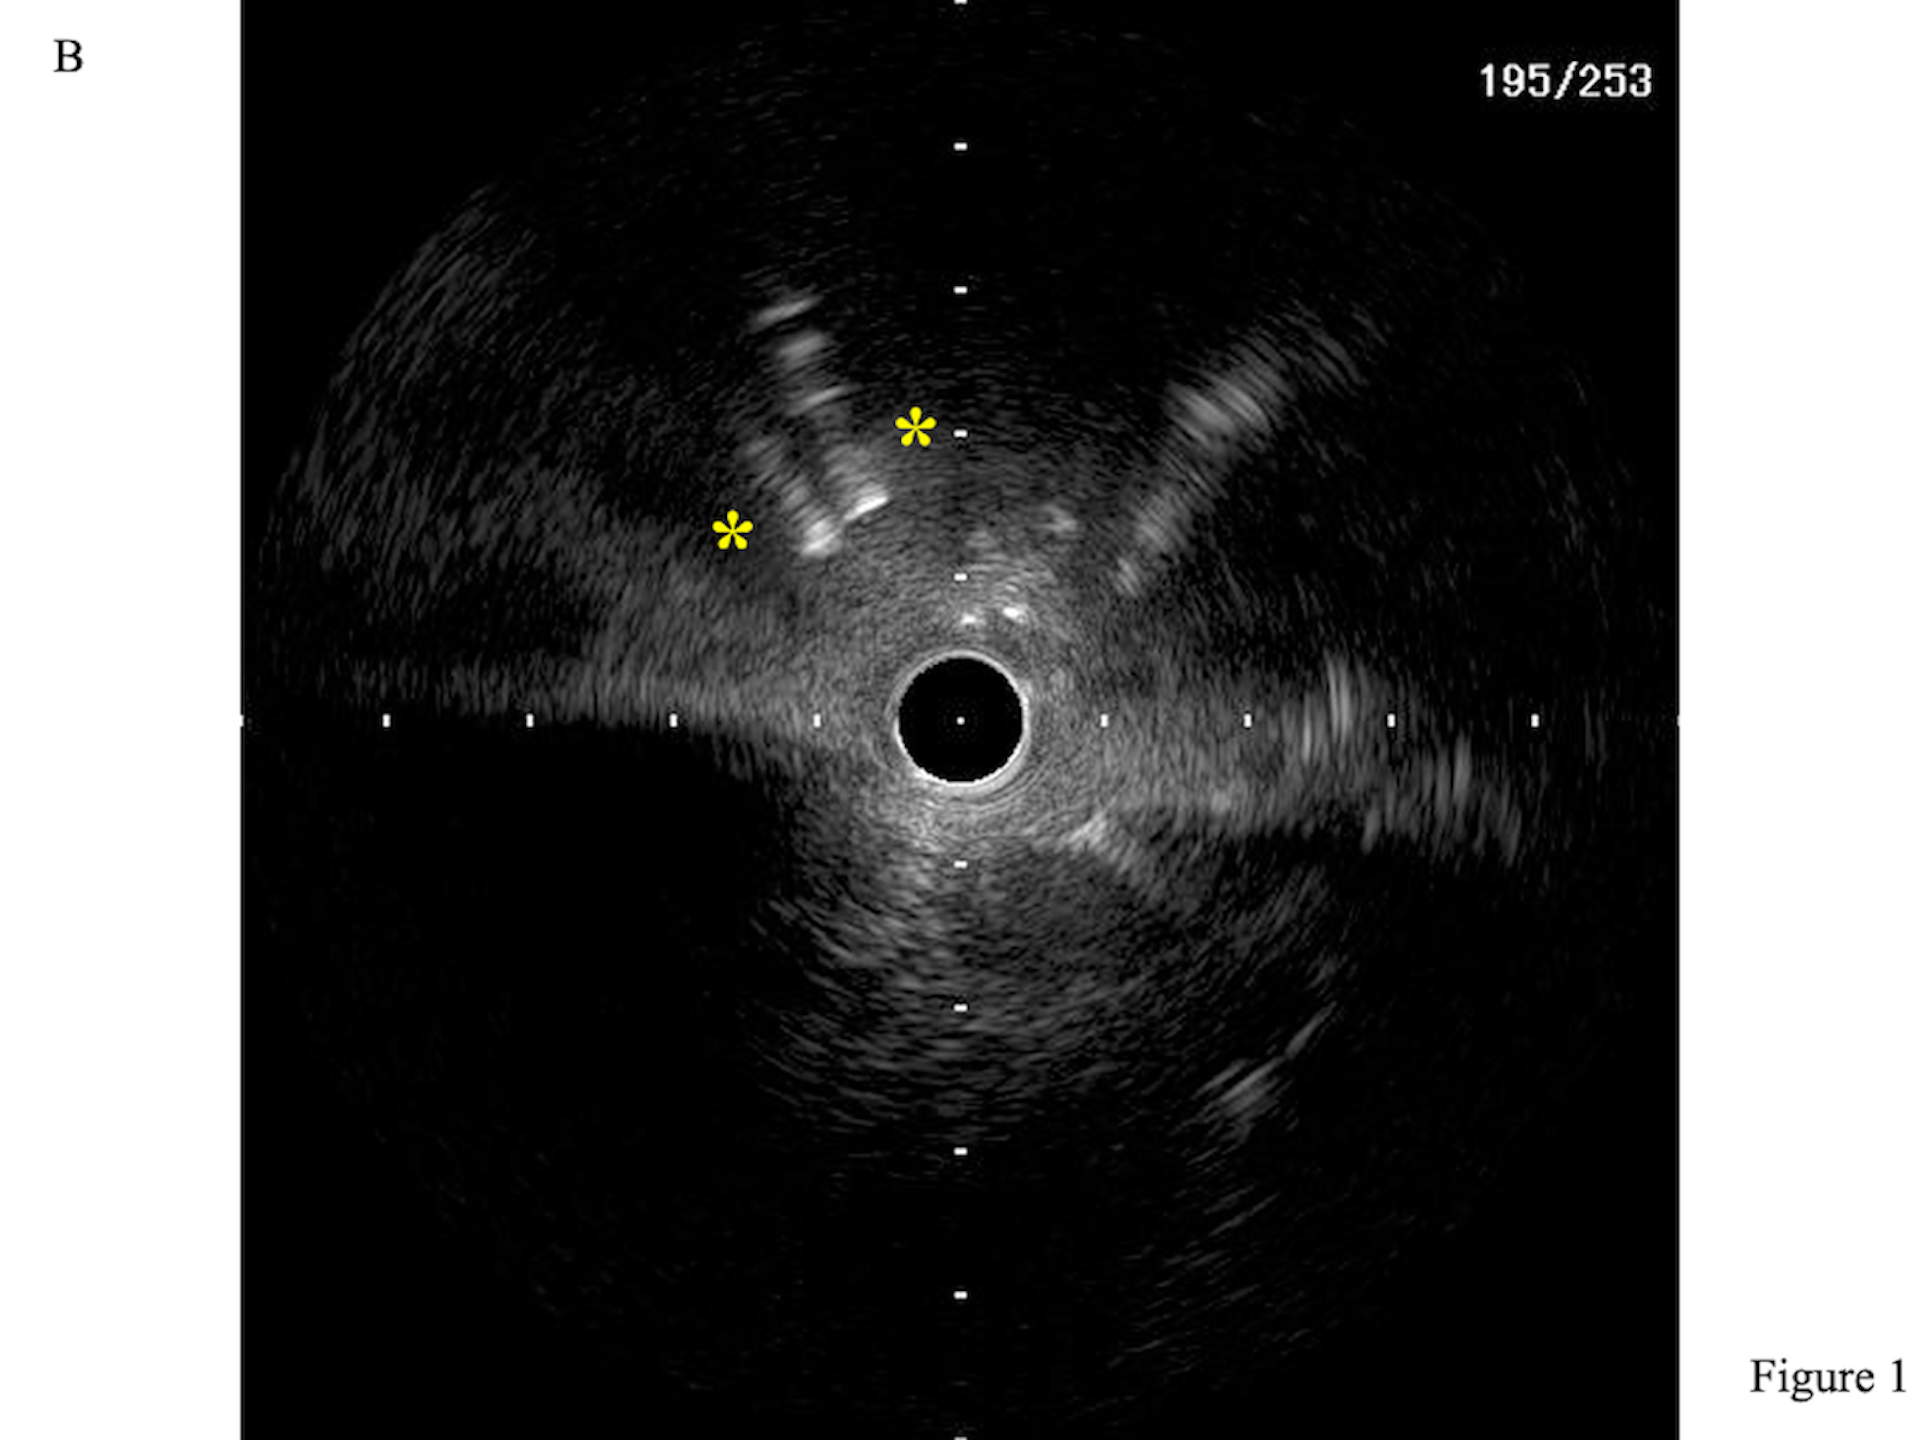

The initial rewiring entered a protruding side strut. A Sasuke dual-lumen catheter (DLC; Asahi Intecc) was inserted along the side-strut wire. The central stent lumen was then wired with another workhorse guidewire (Figure 1A, Video 1), as confirmed by intravascular ultrasound (Figure 1B, Videos 2 and 3). After post-dilatation with a 4.0-mm non-complaint balloon, the final angiographic result was good (Figure 1C, Video 4).